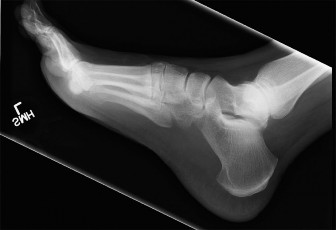

Ankle Arthritis Case: Easing Painful Plantar Flexion Hindfoot

A 48-year-old female presents to your office with worsening right ankle pain. Twenty years ago she sustained …